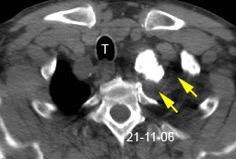

Carcinoma subglótico

Tumor poco frecuente. 1,8% de los tumores laríngeos.

Tendencia a invadir el anillo cricoideo y el esófago.

Ganglios + frecuentes

Mac Neill SD et al. Survival of patients with subglottic squamous cell carcinoma. Curr Oncol. 2018